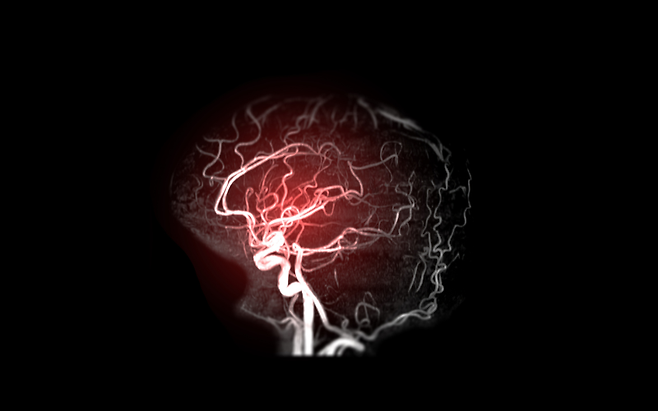

뇌출혈은 뇌혈관이 터지면서 출혈이 발생하는 질환입니다. 특히 고령일수록 혈관이 약해져 발생 위험이 높아집니다.

장기간 고혈압이 지속되면 혈관 벽이 약해집니다. 이 상태에서 혈압이 급격히 오르면 혈관이 터질 수 있습니다.